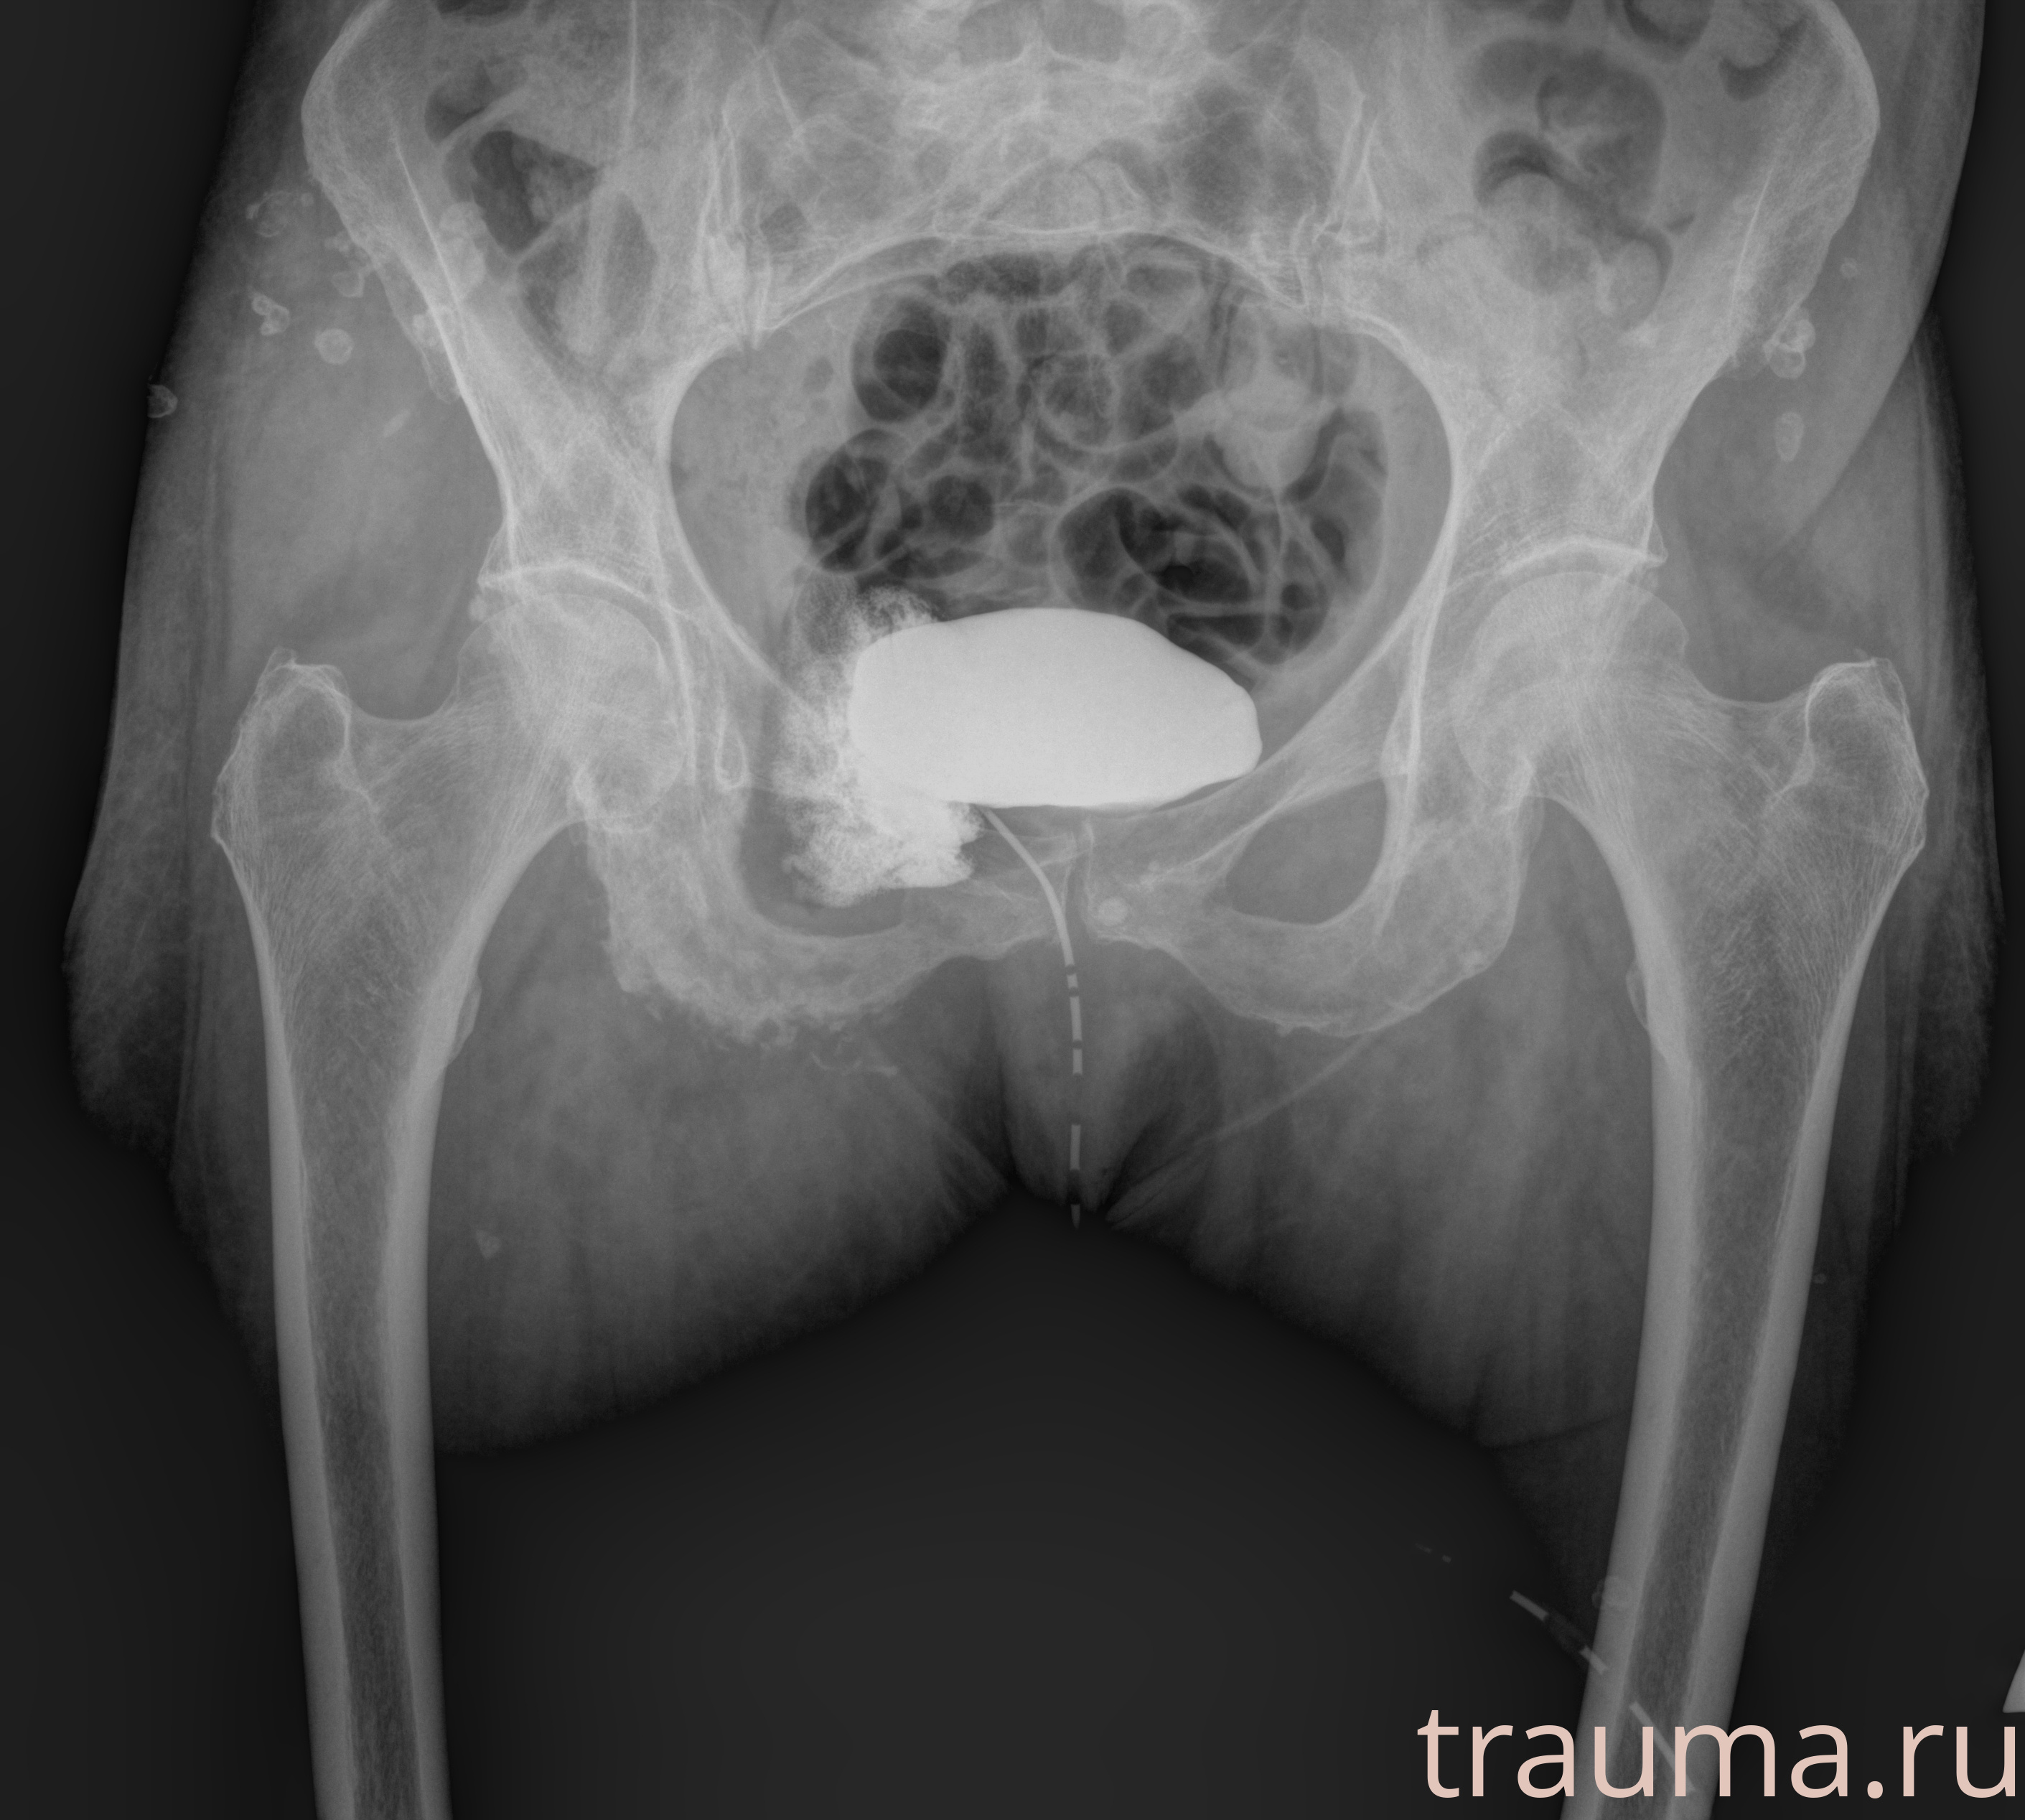

Рентгенограммы

Рентген на дому: по вашему адресу приезжает врач-рентгенолог, травматолог-ортопед с мобильным рентгеновским аппаратом, проводит диагностику травмы или заболевания, делает необходимые рентгенограммы, дает рекомендации по дальнейшему лечению. Получить качественные снимки в домашних условиях возможно благодаря уникальной методике, разработанной МосРентген Центром для института  Склифосовского